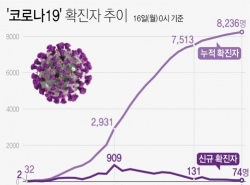

박원순 "구로 콜센터 확진자 전국 129명"…서울외 5명 증가(종합2보)

박원순 "구로 콜센터 확진자 전국 129명"…서울외 5명 증가(종합2보) 음압병실 809개 확보, 실제 사용률 27%…"서울에 심각한 환자 없어" (서울=연합뉴스) 임화섭 기자 = 박원순 서울시장은 16일 오전 10시 기...

| 03-16 11:58